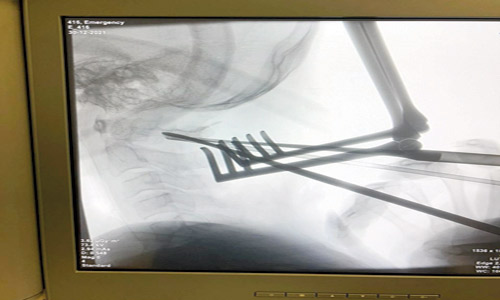

والعملية شديدة التعقيد تطلبت مستوى عالياً من الخبرة الجراحية المتخصصة، وتم تثبيت الفقرتين الأولى والثانية للمريض خلال 4 ساعات. وقام الفريق بتعديل الكسر وتثبيت الفقرتين العنقيتين الأولى والثانية. وتمثلت صعوبة العملية الجراحية في وجود شرايين رئيسية للدماغ والحبل الشوكي في هذه المنطقة وقربهما من مكان تثبيت المسامير.

وقام بالعملية استشاري جراحة المخ والأعصاب والعمود الفقري الدكتور رامي الشمراني والدكتور سامي المحيميد. وتمت العملية بنجاح دون أي مضاعفات.